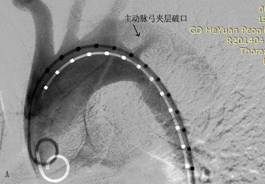

图1 患者男,46岁,胸痛5小时急诊入院,诊断为主动脉夹层(Standford B型),入院1周后行主动脉夹层腔内修复术,术后1周临床治愈出院。A为治疗前造影,B为覆膜支架修复破裂口后。